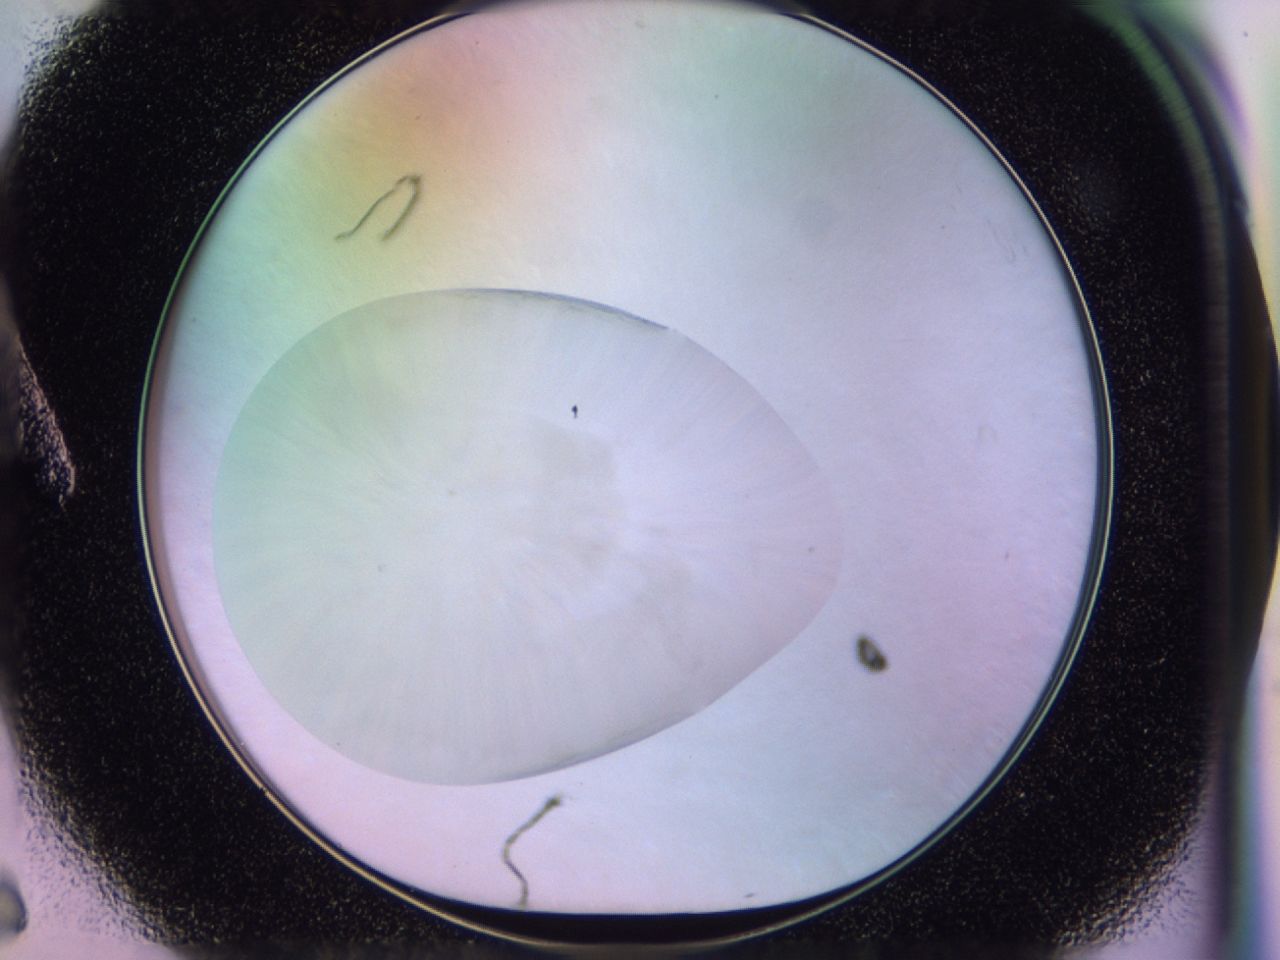

Image 2253

Score

Precipitate

Organization

GSK

00pk_A6_ImagerDefaults_3.jpg